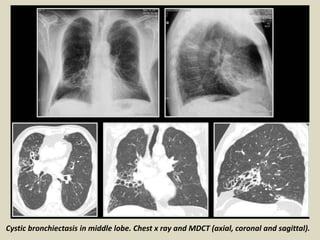

Cystic bronchiectasis in middle lobe. Chest x ray and MDCT (axial, coronal and sagittal).

HRCT features ofNSIP include extensive ground-glass areas in the lung (black arrows) and traction bronchiectasis. This bronchiectasis frequently shows a parallel course through the lung, well depicted by sagittal reconstruction in D (black dotted arrows). There is no honeycombing in the lung. Cystic bronchiectasis is generally well documented by MPR images

• 70.

Cystic bronchiectasis inmiddle lobe. Chest x ray and MDCT (axial, coronal and sagittal).